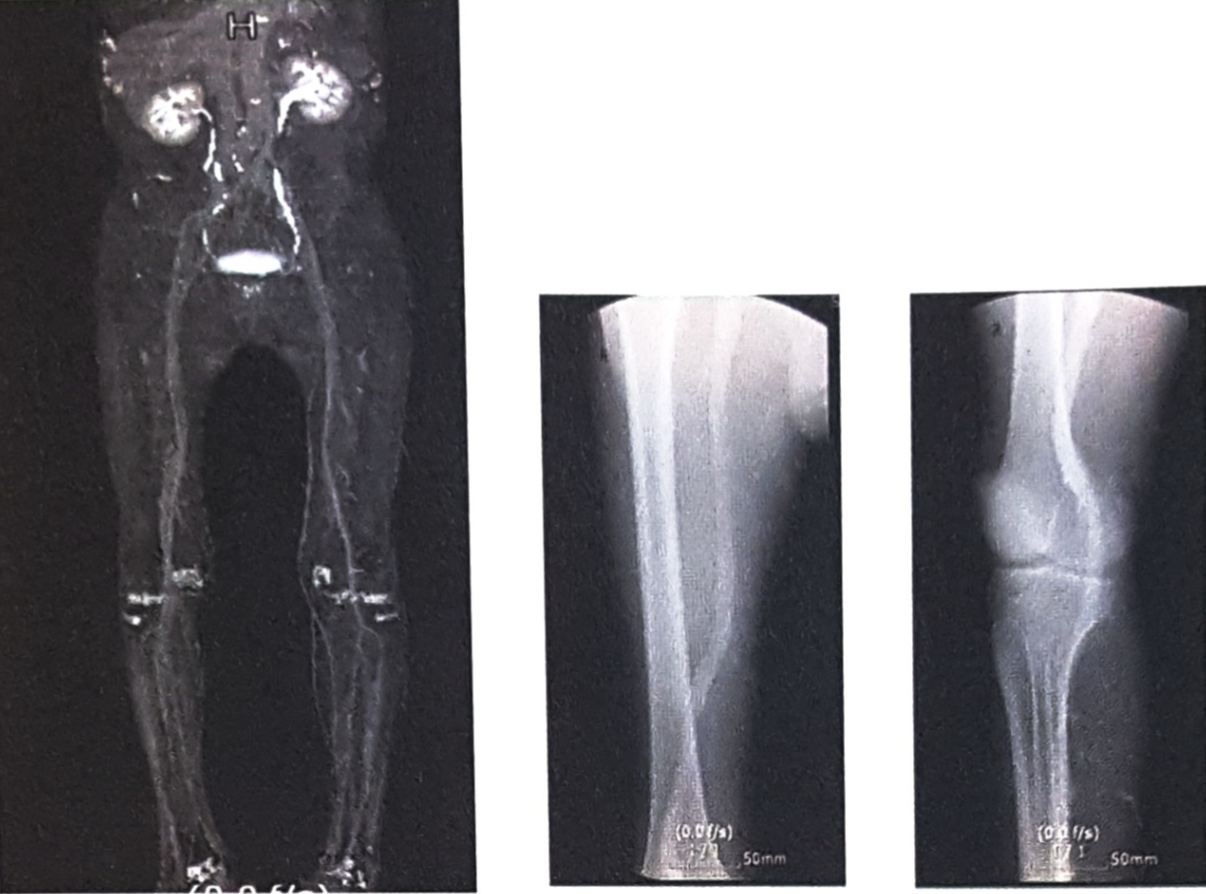

CT(Computed Tomography, 전산화단층촬영)검사는 신체의 일정 원하는 부위에서 단면을 깨끗한 2차원 영상으로 볼 수 있는 검사입니다. 촬영이 끝난 후 이러한 2차 단면영상을 컴퓨터를 이용하여 삼차원(3D)영상으로 재구성하면 동맥이 특별히 잘 보일 수 있도록 입체적인 영상도 얻을 수 있습니다.

대동맥부터 다리 전체의 동맥

다리의 무릎아래 동맥